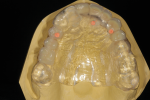

A male patient visited prosthodontist Young S. Kang, DDS, FACP, for restoration of the missing front teeth (Figure 1). Three years prior to the initial visit, the patient suffered multiple fractures to the head, including bilateral subcondylar fractures and bilateral coronoid fractures, from a motor vehicle accident. During the recovery period, the patient underwent extensive dental treatments (Figure 2 through Figure 4).

For diagnostic purposes, the prosthodontist mounted diagnostic casts on a semi-adjustable articulator (Stratos 300, Ivoclar Vivadent, ivoclarvivadent.com) with a centric relation record from a Gothic arch tracing device (Massad Jaw Relator, LeeMark Dental, leemarkdental.com) (Figure 5). Additionally, in order to investigate the influence of the facial trauma on the patient's condyles, the prosthodontist performed a computerized mandibular movement analysis (Cadiax® Compact 2, Whip Mix, whipmix.com).

Based on the diagnostic wax-up (Figure 6) and other clinical findings, the prosthodontist made the following diagnosis: (a) partial edentulism with missing teeth Nos. 3 through 5 and 8 through 12 (Kennedy Class 3 mod I1); (b) irregular plane of occlusion due to supra-eruption of teeth Nos. 29 and 30; (c) low horizontal condylar inclination of the right condyle (5° vs. 42° of the left condyle); and (d) moderate tooth wear (Smith and Knight Class Two2).